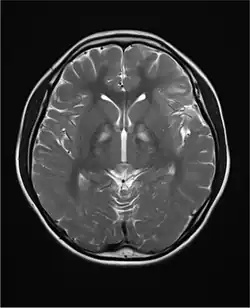

- zmiany w istocie białej[2]